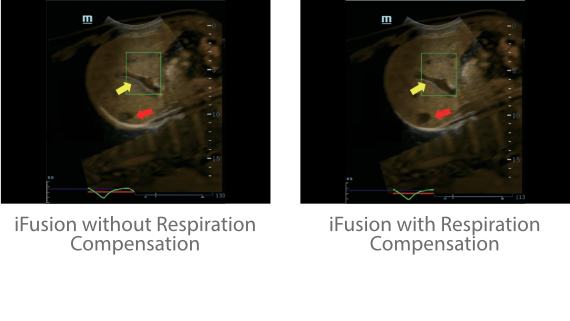

?? Resona 7? ???? ??? ?? ???? ??? ??? ???? ??? ?? ???? V Flow? ?? CNS ??? ?? 3D ??? ???? ?? ???? ?? ??? ?? ?? ?? ??? ??????. ???? ??? ??? ?? ?? ??? ??? ?? ?? ??? ??? Resona 7? ??? ???? ???? ??? ??? ??? ????.